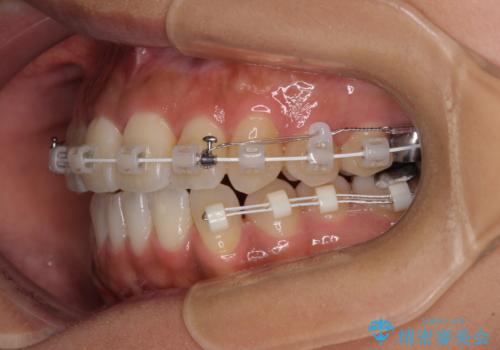

- 審美装置

上顎骨の横幅が狭く、歯列が混み合っていたため、急速拡大装置により側方拡大し、咬み合わせと歯列を改善することとしました。

下顎は部分的に咬み合わせに問題があったため、部分的な装置を付けることとしました。